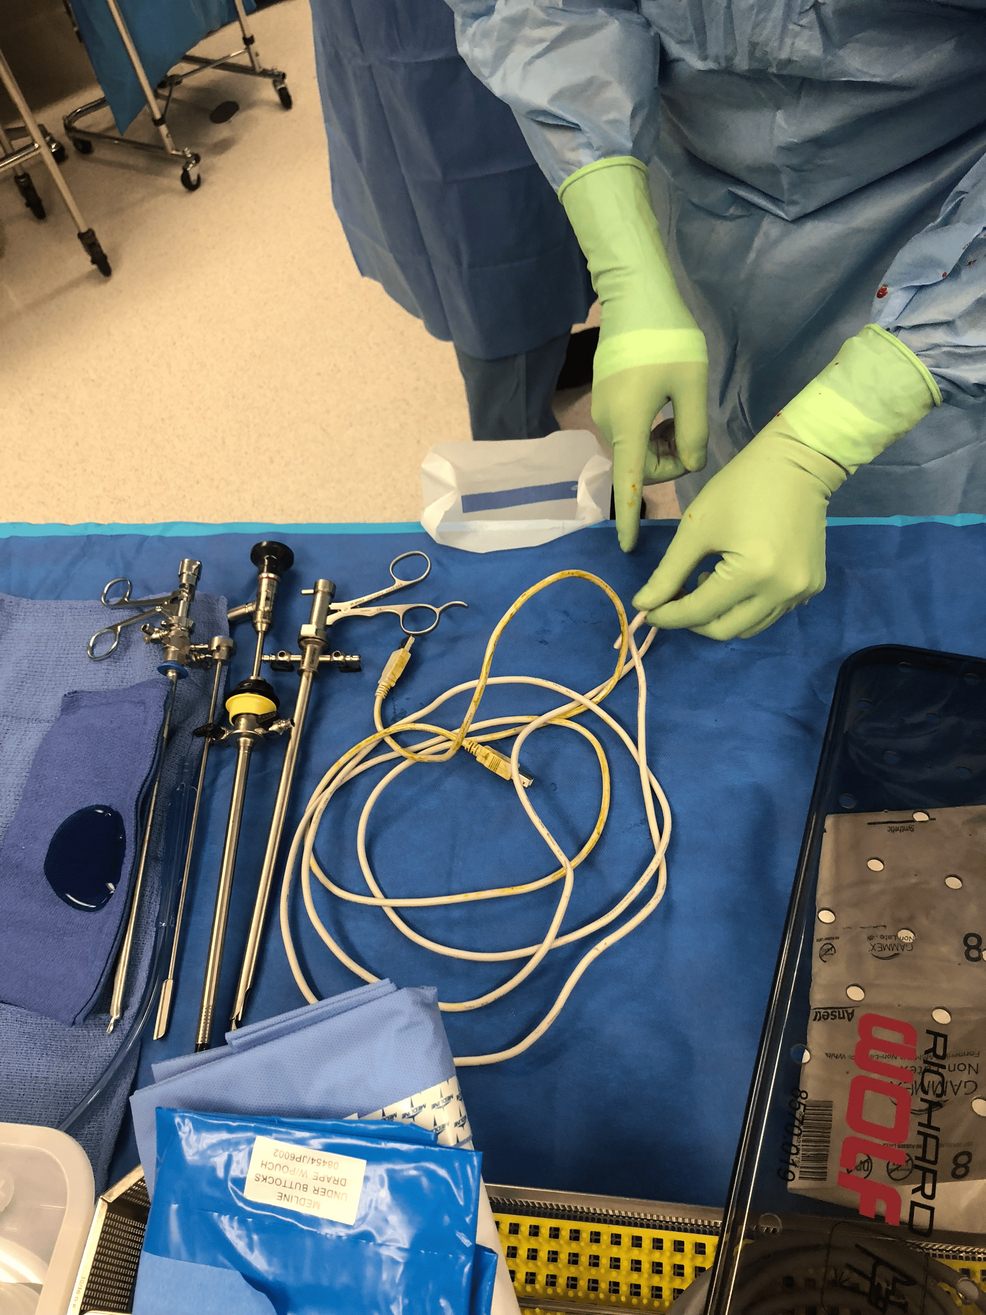

A equipe médica realizou uma cirurgia sob anestesia geral, inserindo uma câmera pela uretra junto ao cabo para removê-lo, minimizando danos aos tecidos. Após o procedimento, uma verificação adicional mostrou apenas lesões menores na uretra do paciente.